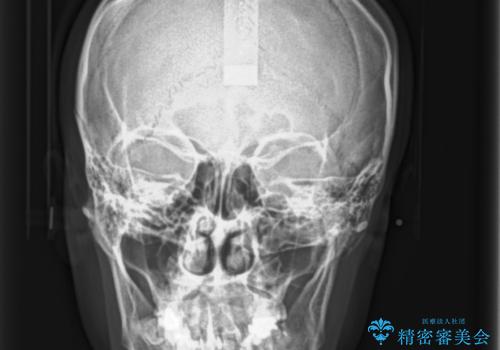

- 前歯の歯並びが気になることを主訴に来院された患者様です。

顎が小さく歯を並べるためのスペースが足りないため、

上下の前歯の歯と歯の間をすく処置(ディスキング)を行いました。

矯正装置:インビザラインフル (初回13stage+リファインメント11stage:計1年)

なお、左下の奥歯(左下7)は状態が悪く保存不可能と判断し矯正前に抜歯しております。